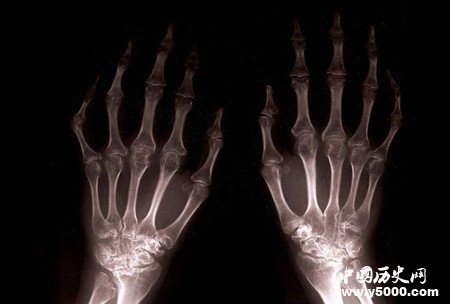

接着,伦琴又让他的夫人把手放在雷钠管和胶板中间,结果,夫人手上的每块骨头以及手上戴的戒指都照出来了。

这一偶然发现使伦琴感到兴奋,他把其他的研究工作搁置下来,专心致志地研究这种射线的性质,对于这种未知的射线,伦琴把它命名为“X射线”。经过几周的紧张工作,他发现了下列事实:(1)X射线除了能引起氰亚铂酸钡发荧光外,还能引起许多其他化学制品发荧光。(2)X射线能穿透许多普通光所不能穿透的物质;特别是能直接穿过肌肉但却不能透过骨骼。(3)X射线沿直线运行,与带电粒子不同,X射线不会因磁场的作用而发生偏移。

后来,人们运用X射线造出X光透视器,可以透视人体的内脏和骨骼,使医生能正确发现病人的病因,挽救了千千万万人的生命。